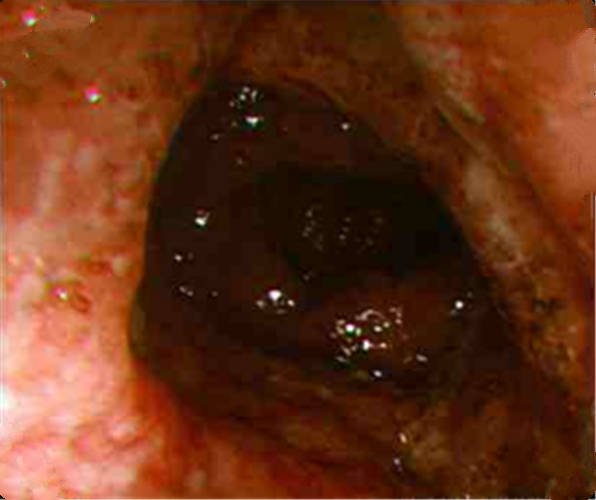

纖維結腸鏡檢查

慢性結腸炎圖片

缺血慢性結腸炎患者

缺血性慢性結腸炎的

缺血性慢性結腸炎患者